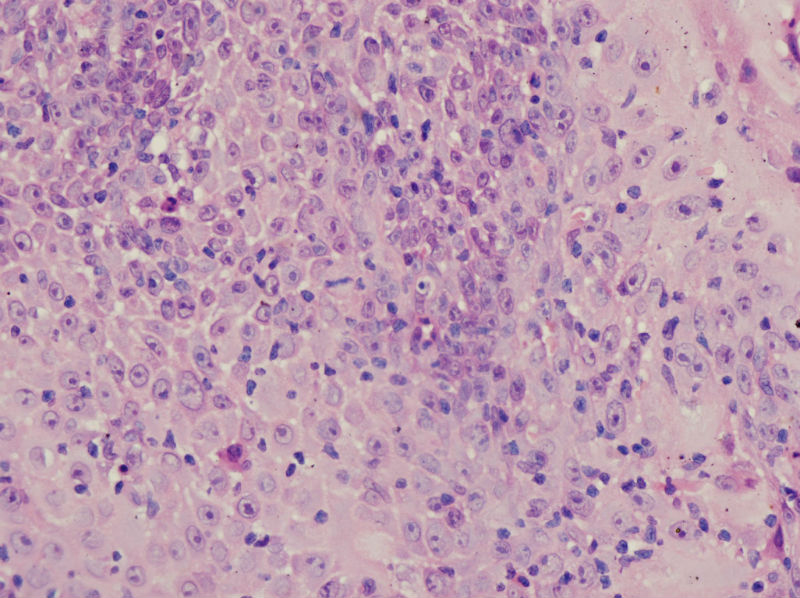

男,45岁,上唇菜花样肿物,请老师指教

图3

高分化鳞癌

倾向于鳞癌,恶黑不除外。